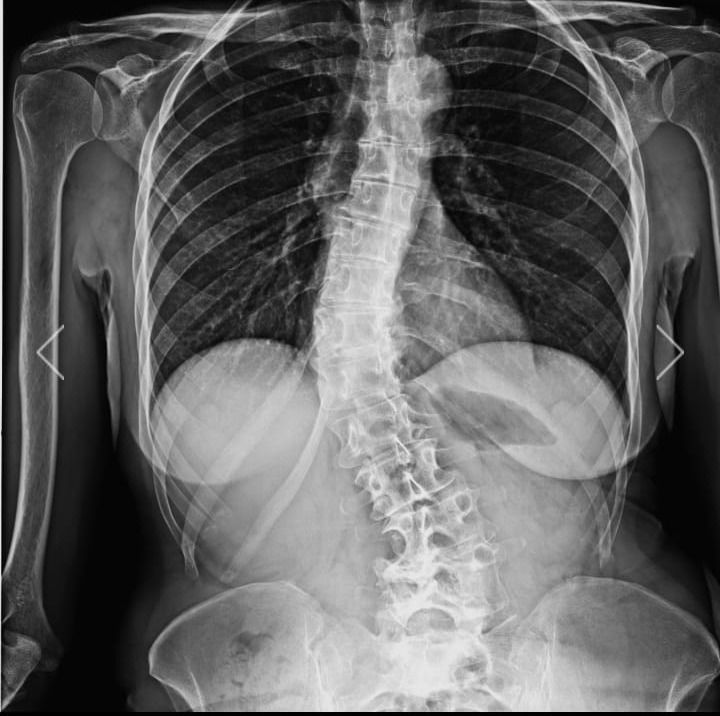

Foto e video